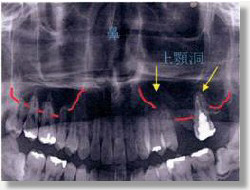

上顎桐底に歯の根の先が突き出ており、歯による蓄膿症を起こしやすい